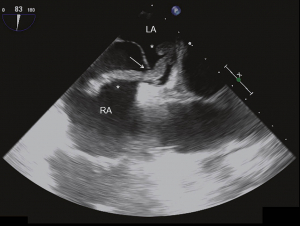

Abb. 5: Intraoperative transösophageale Echokardiographie mit Blick auf die Atria und das interatriale Septum.

Es zeigt sich, dass der Thrombus (*) nun durch ein persistierendes Foramen ovale (Pfeil) in das linke Atrium prolabiert. RA bedeutet rechtes Atrium und LA linkes Atrium.